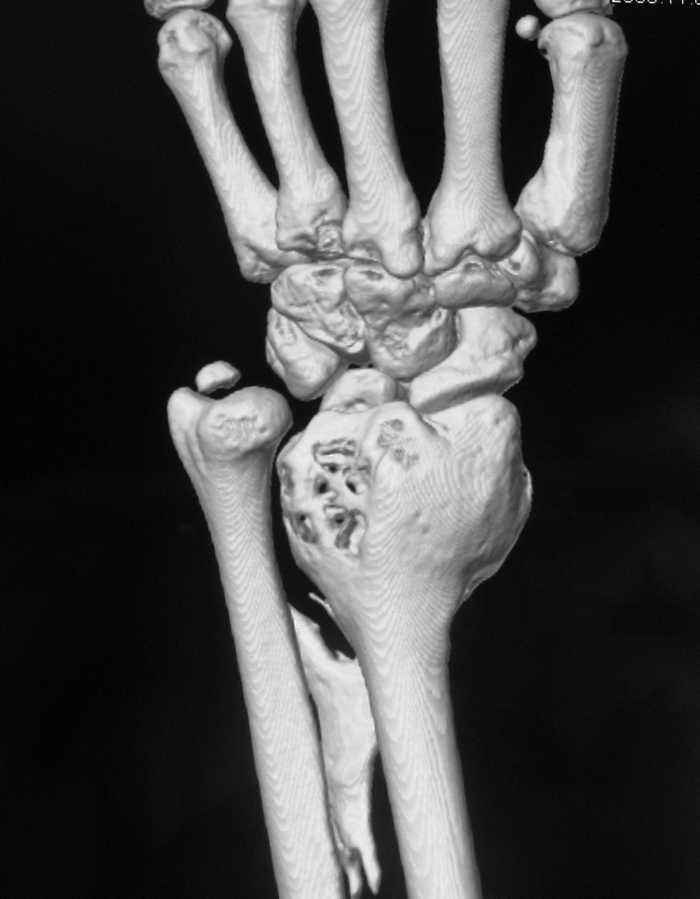

ОБК дистального эпифиза левой лучевой кости

Здравствуйте, уважаемые коллеги! На приём обратилась молодая женщина 28 лет с жалобами на наличие образования в области левого лучезапястного сустава.

Болевой синдром умеренный, "ночных" болей нет. Полтора года назад - патологический перелом дистального эпиметафмза левой лучевой кости. В Областном онкодиспансере выполнена открытая биопсия патологического очага.

Морфологическое заключение: остеобластокластома без признаков малигнизации.